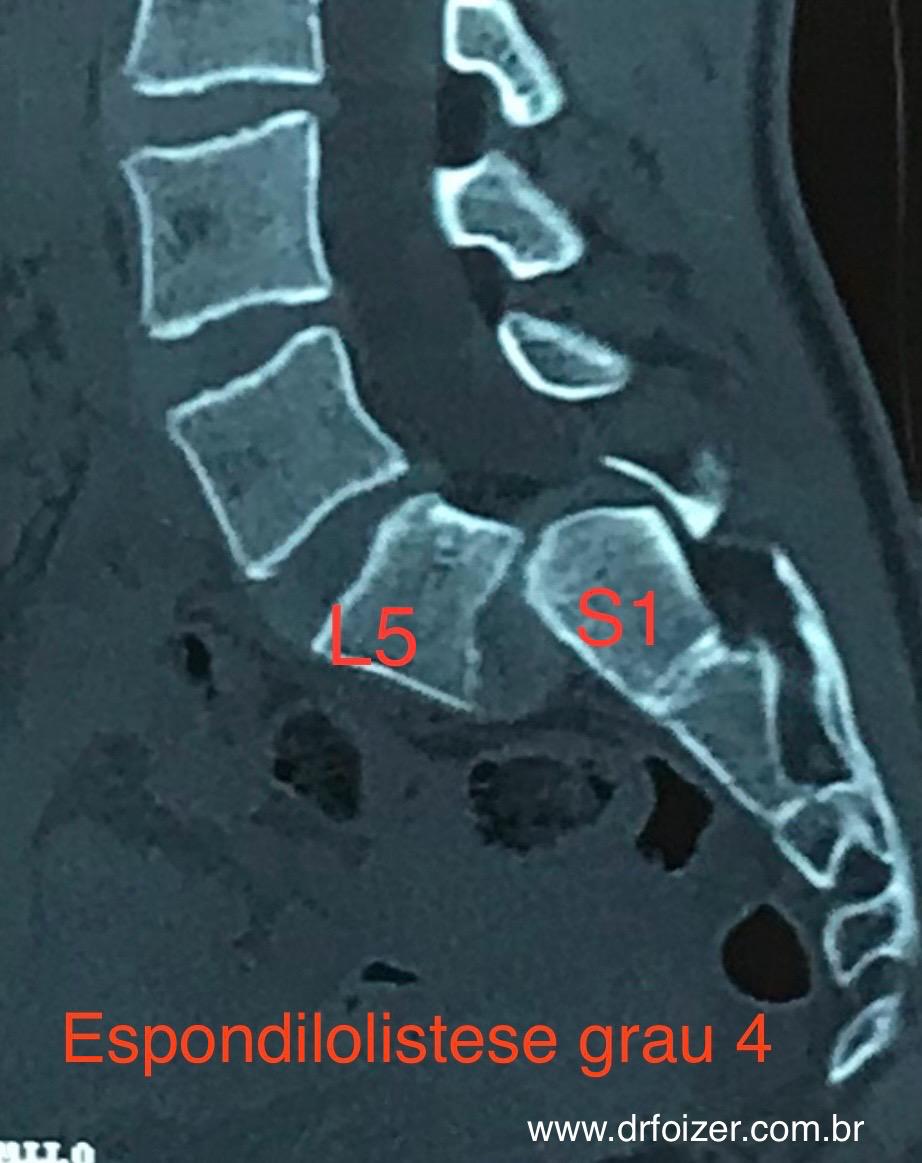

- Espondilolistese: quando há escorregamento vertebral com sintomas e falha do conservador, a estabilização (fusão) pode ser indicada.